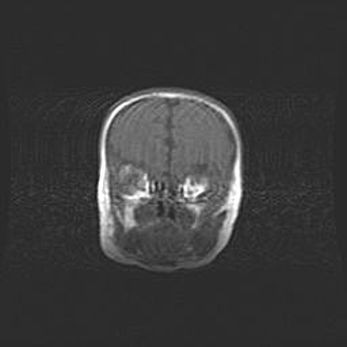

Открытая гидроцефалия.

Возраст: 9 месяцев 12 дней

Вес: 6800 г

Пол: мужской

Окружность головы: 41,5 см

Срок гестации: 28 недель

Гидроцефалия головного мозга у новорожденных имеет характерный признак: опережающий рост окружности головы приводит к визуально хорошо определяемой гидроцефальной форме сильно увеличенного в объёме черепа. Детские неврологи определяют следующие симптомы гидроцефалии у грудничков: выбухающий напряжённый родничок, частое запрокидывание головы, смещение глазных яблок к низу.